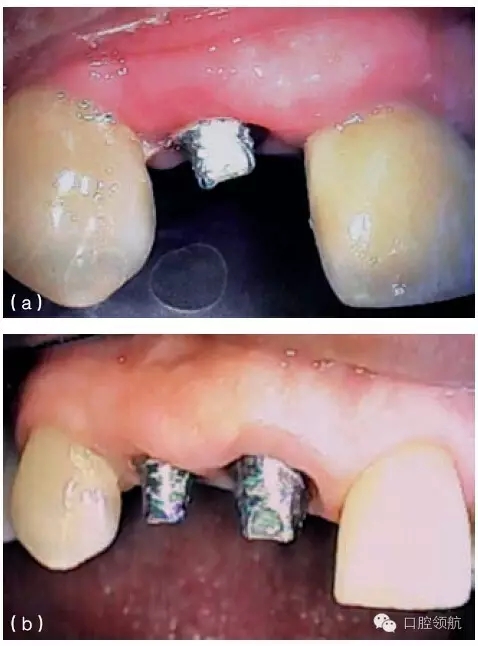

種植體周圍有一個淺的組織袖口,但這個袖口可能位于鄰近牙或種植體的根方。當種植體植入時,牙槽嵴已經(jīng)發(fā)生垂直吸收,就會出現(xiàn)這種情況。當種植體植入這些未行位點恢復的區(qū)域時,種植體跟鄰牙間的牙齦不在同一水平,這將造成不平整的牙齦形態(tài)。如果修復體在美學區(qū)域內(nèi),使用齦色瓷(或復合材料)可以部分遮蓋牙齦高度差異(圖9.24a,b)。另外,當一個長的臨床牙冠可以被患者的嘴唇遮蓋時,這種方案也是可取的。因而,在制訂治療計劃的時期,就要考慮到是否存在不一致的骨水平。為了克服這些不一致的情況,獲得滿意的修復效果,使用CT檢查及外科模板,有利于評估預期修復體與缺失軟硬組織之間的

關系。如果這些不規(guī)則的差異,在美學方面不能讓患者滿意,醫(yī)生在診斷和進行外科手術之前,必須充分評估及討論缺失組織的再生潛力。

圖9.24 (a) 由于種植體植入前,沒有進行充分的位點恢復,最終在修復體唇面輔以齦色瓷,以彌補軟組織的不足。(b)口內(nèi)全景觀,全口烤瓷熔附金屬修復體,粘結固位,注意左側(cè)側(cè)切牙牙齦區(qū)域的齦色瓷。